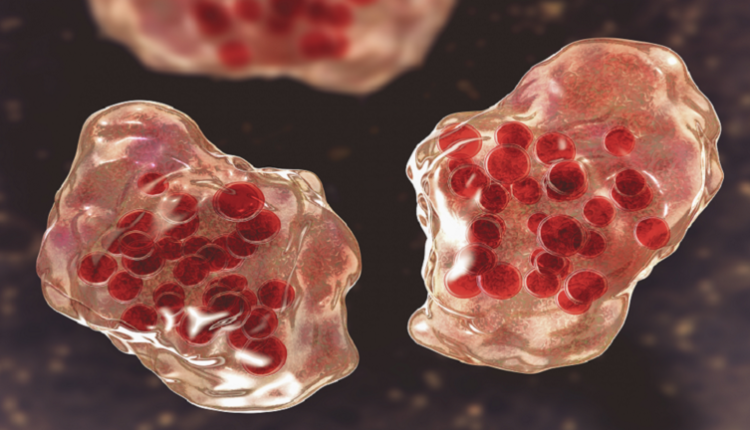

حذر خبراء من أن الوباء التالي، الذي يطلق عليه اسم “الوباء الكبير”، قد يطلق العنان لأكثر الأمراض المعدية فتكا التي عرفتها البشرية.

وتضم عائلة paramyxovirus أكثر من 75 فيروسا، بما في ذلك فيروس النكاف والحصبة والتهابات الجهاز التنفسي، وقد تمت إضافتها إلى قائمة مسببات الأمراض الوبائية، في المعهد الوطني للحساسية والأمراض المعدية الأمريكي، التي يجب مراقبتها.

ويمكن لأحد الفيروسات، فيروس Nipah، أن يصيب الخلايا بمستقبلات تنظم ما يدخل أو يخرج من الخلايا التي تبطن الجهاز العصبي المركزي والأعضاء الحيوية.

ويشير العلماء إلى أنه على عكس الإنفلونزا و”كوفيد-19″، فإن فيروسات paramyxovirus “تتغير بشكل سريع”، ويبدو أنها لا تتحور أثناء انتشارها، لكنها أصبحت “جيدة جدا في الانتقال بين البشر”.

وقال مايكل نوريس، الأستاذ المساعد في جامعة تورنتو، في بيان: “فقط تخيل لو ظهر فيروس paramyxovirus وكان معديا مثل الحصبة ومميتا مثل Nipah”.